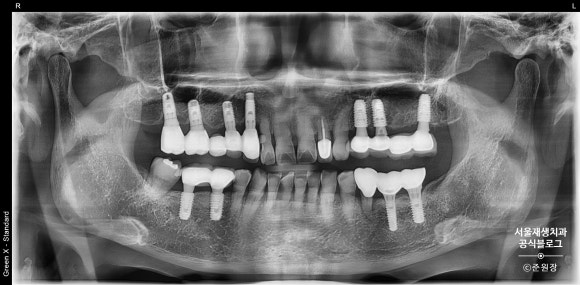

개원 3일차 어느 오후,

준원장에게 멋쟁이 60대 여성 환자분이 찾아오셨습니다.

왼쪽 아래 치아가 시리고 흔들려요!

파노라마 사진에서 원인 치아를 찾아보아요.

치아들의 단체사진입니다.

준원장은 파노라마 엑스레이를 보는 순간 원인치아를 찾아낼 수 있었답니다.

원인은 왼쪽 아래(사진상 우측하단입니다), 임플란트 앞에 있는 자연치였습니다.